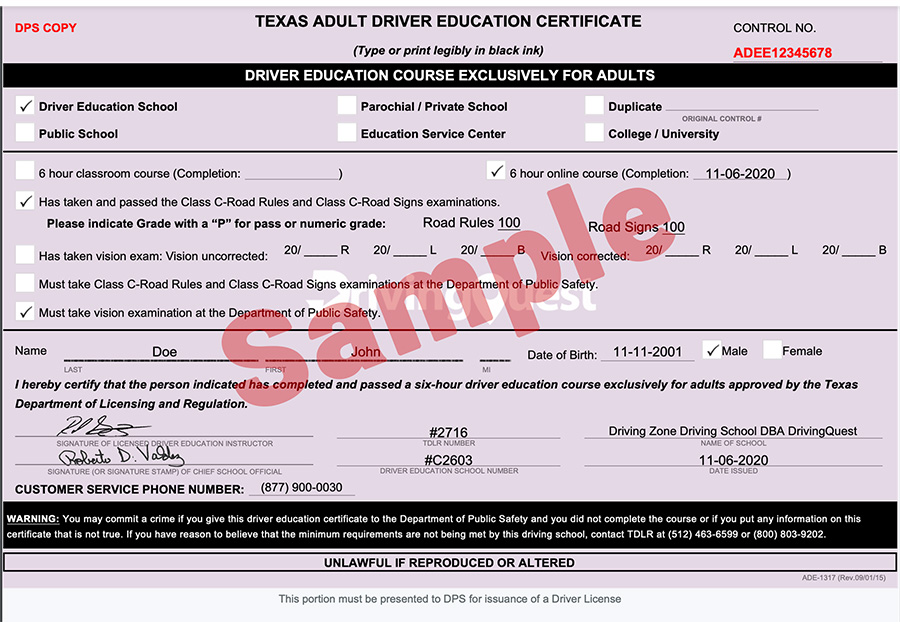

I carry out more than a hundred of these treatments - or blepharoplasties, as they are known - a year, and more than half are for medical reasons, including reduced vision, inflammation and ingrowing eyelashes.Īge is a major factor in heavy or sagging eyelids. He says: Eyelid surgery isn't just a cosmetic procedure. Raj DAS-BHAUMIK is a consultant oculoplastic surgeon at the London Eye Hospital and Moorfields Eye Hospital NHS Foundation Trust In addition to age, smoking, not using sunscreen and drinking too much contribute towards baggy eyelids You wouldn't know I'd had it done - there's virtually no scar and I have no irritation. I was back at school a few days after the surgery. I had slight bruising for a few days, then two weeks after the operation the stitches were removed. That evening, I was allowed to remove them and, although my eyes were tender, I was surprised at just how comfortable I felt. My husband Richard dropped me off at 7pm, and by 9pm I was on my way home with two gauze bandages over my eyes. Throughout the procedure I felt a slight tugging sensation, but nothing too unpleasant.

I had the surgery last October with just a local anaesthetic in my eyelid (I had a patch covering my other eye so I could not see what was going on). The NHS doesn't routinely fund heavy eyelid removal, but luckily I had private medical insurance.

Mr Das-Bhaumik said he could remove the excess skin with a special laser instead of a scalpel, which meant a faster recovery time. This meant that some lashes were rubbing against the eye's surface, causing the painful scratching sensation. It was worse in the left eye and the skin was drooping downwards so my eyelashes were pointing inwards. He told me the problem was that my eyelids were too heavy. It became difficult to read and my eyes were sore because I kept rubbing them.īy this time I'd had enough, and I returned to my GP who referred me to consultant eye surgeon Mr Raj Das-Bhaumik. However, over the next few weeks the irritation returned. She removed it with tweezers and, after a few days, it was bliss not to feel the scratching sensation. I have incredibly fair eyelashes which is possibly why no one had spotted it. So I went back to my optician and, after examining my eye close-up, she found an ingrowing eyelash. My optician then referred me to an NHS eye clinic which also couldn't find anything wrong. My GP couldn't see anything that might be causing it and prescribed anti-inflammatory drugs. Then my eyes started to get really painful: I couldn't sleep because my left one was sore and inflamedĮventually both my eyes were bloodshot, swollen and watering constantly. In February last year, I visited my optician, but she couldn't find anything and gave me antibiotic eye drops to soothe the irritation. At first, I blamed the heat, but then it started happening at home. The problem would always occur abroad on our annual holiday.